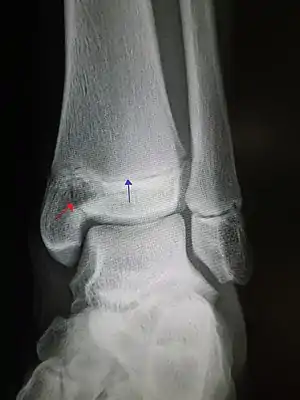

| Pott's fracture[5] | Percival Pott | bimalleolar fracture of the ankle | eversion of ankle | Pott's fracture at Who Named It? | |

| Le Fort's fracture of the ankle | Léon Clément Le Fort | vertical fracture of distal fibula with avulsion of medial malleolus | LeFort's fracture of the ankle at Who Named It? | ||

| Gosselin fracture | Leon Athanese Gosselin | V-shaped distal tibia fracture extending into the tibial plafond | Gosselin's fracture Archived 2017-09-08 at the Wayback Machine at TheFreeDictionary.com | ||

| Maisonneuve fracture | Jules Germain François Maisonneuve | spiral fracture of proximal fibula | external rotation of ankle | Maisonneuve fracture Archived 2020-09-22 at the Wayback Machine at Wheeless' Textbook of Orthopaedics online |